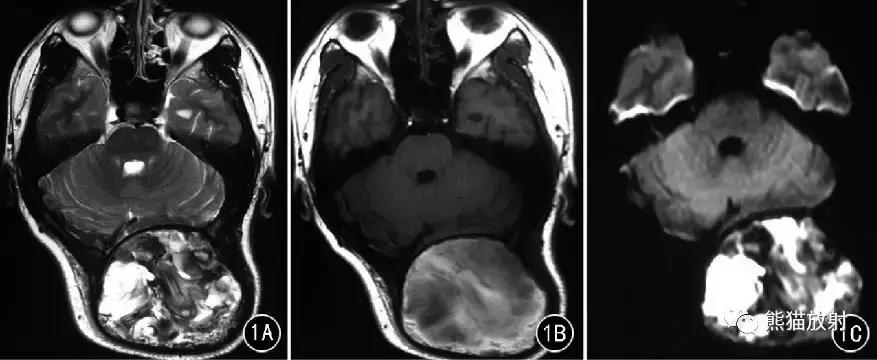

图1 男30岁。颅骨骨内型假肿瘤。枕部巨大肿块,枕骨内外板膨胀、受压,脑组织受压变形; T2WI(A) 、T1WI(B) 和DWI(C) 均呈高、低混杂信号。